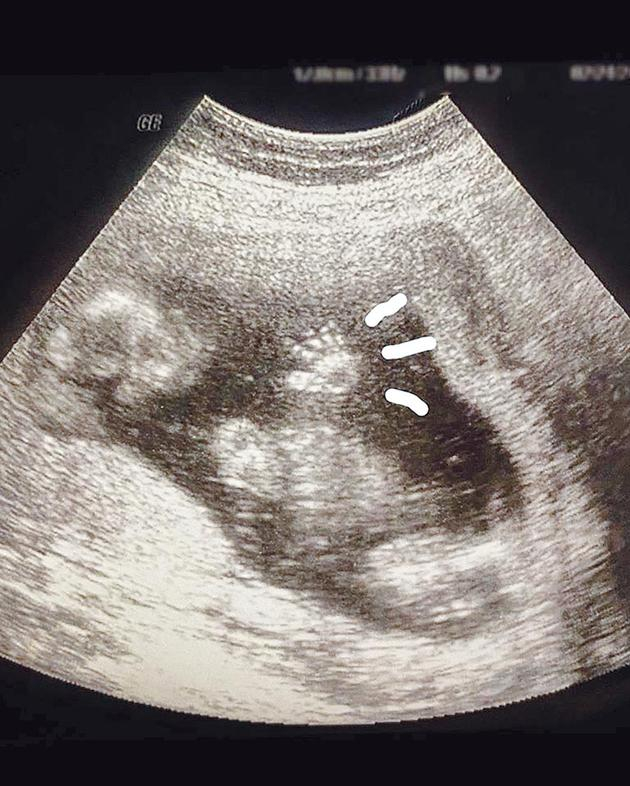

摘要: 深演员谭艾珍女儿、36岁的欧阳靖,14日宣布和交往5年的日本摄影师男友RK登记结婚,并晒出超音波照片分享怀孕5个月的喜讯。

新浪娱乐讯 据台湾媒体报道 资深演员谭艾珍女儿、36岁的欧阳靖,14日白色情人节宣布和交往5年、大她1岁的日本摄影师男友RK登记结婚,并晒出超音波照片分享怀孕5个月的喜讯。谭艾珍昨接到各方祝福,表示不管是孙子或孙女,她已经先帮宝贝孙取个小名叫“皮卡丘”,笑说“因为我爱抓宝,刚好金鼠年,小皮又是一种日产鼠类。”